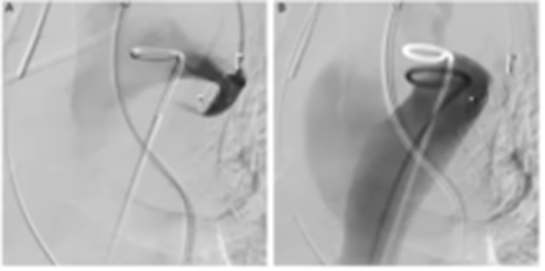

前瞻性的研究对于EVAR术前单侧或双侧栓塞ⅡA术后臀肌跛行发生情况进行比较,表明在术后6个月后臀肌跛行状况有所改善,但双侧髂内栓塞似乎比单侧栓塞更严重。因此,建议至少保留一侧ⅡA。对于术后对运动要求不高的患者,盆腔血供更丰富,出现臀肌跛行的概率更低。而轻微臀部跛行并不会影响患者生活质量。而对运动、性生活需求高的患者,也可通过三明治、IBD/IBE、带分支支架等方法进行髂内重建。2016年,Falkenberg等提出一种新的血管内技术——主动脉夹层裂口栓塞技术,以避免部分因主动脉弓慢性小夹层破口导致动脉瘤扩张的患者中进行开放手术重建。技术特点是使用AVP Ⅱ从假腔侧通过近端破口推进,作为破口孔内的密封按钮展开,使得AVP Ⅱ的1个瓣在真腔内,其余2个瓣在假腔内。该技术应用于4例累及主动脉弓的慢性夹层患者,其中3例成功栓塞了胸主动脉假腔,随访期间血栓形成和主动脉内径缩小。由此可见,采用AVP Ⅱ作为封闭按钮对主动脉弓近端小夹层破口进行血管内封闭是可行的,在选定的慢性主动脉弓夹层和继发性动脉瘤扩张患者中,可能是开放手术重建弓的替代方案。